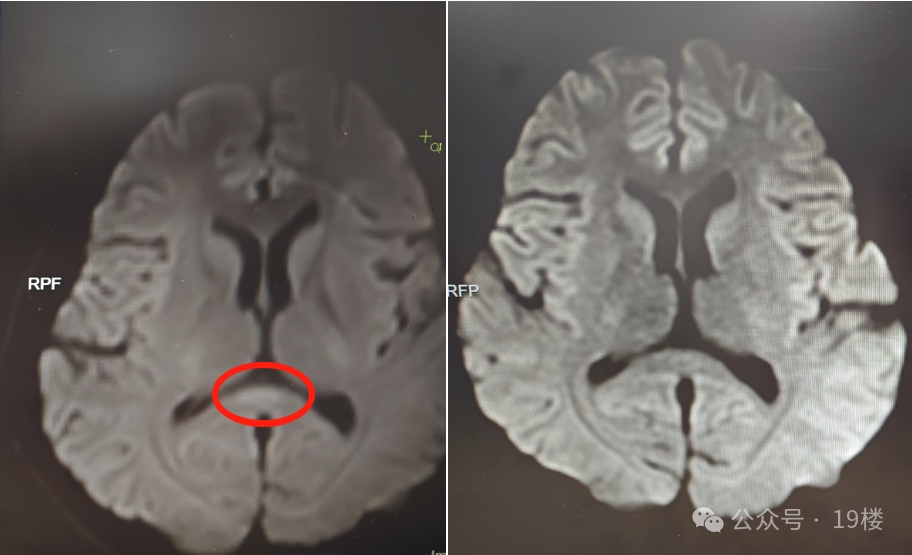

为寻求进一步诊疗,6月初,几近崩溃的家人带阿婷来到广东三九脑科医院求诊。该院神经内六科医生接诊后,初步判断为脑炎。完善血清、脑脊液检测等,结果不支持颅内感染及自身免疫性脑炎,进一步完善细胞因子等炎症指标,结合核磁共振等,最终诊断阿婷为副感染性脑病。

▲治疗前(左)核磁共振提示胼胝体压部病变

好在接受相应治疗后,阿婷的意识逐渐恢复,情绪日趋稳定,已于近日康复出院。